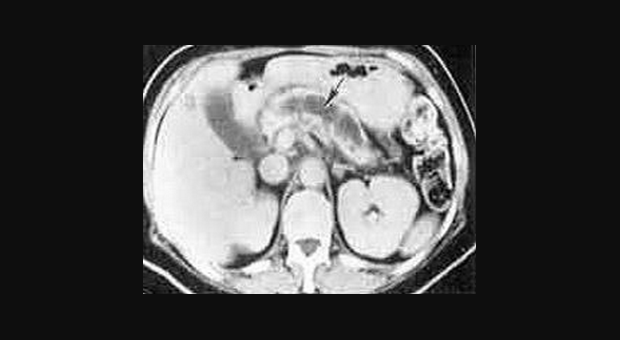

Иллюстрация №4: РХПГ при хроническом панкреатите (Изменения по типу "жемчужной нити")

Амилаза и липаза сыворотки может соответствовать норме или быть незначительно повышена. У 5-10 % пациентов с хроническим панкреатитом компрессия дистальной части общего желчного протока ведет к увеличению билирубина сыворотки и щелочной фосфотазы. Мальабсорбция жира ведет к увеличению его экскреции с калом (более 7 грамм в день). Выявление панкреатических кальцификатов при рентгенографии, УЗИ или компьютерной томографии является диагностическим критерием хронического панкреатита. Эти кальцификаты обнаруживаются в примерно 25-60 % всех случаев хронического алкогольного панкреатита и у 35-80 % пациентов с панкреатитом другой этиологии. Компьютерная томография может также выявить локальное увеличение размеров поджелудочной железы, ее атрофию, расширение панкреатического протока или псевдокисту. РХПГ является наиболее чувствительным и специфическим визуализирующим исследованием в диагностике хронического панкреатита (рис. 3).

Из-за риска развития панкреатита в результате выполнения РХПГ эта диагностическая процедура должна применяться только когда неинвазивные исследования являются малоинформативными. Новые, более современные виды исследований, как ядерно-резонансная холангиопанкреатография и эндоскопическое ультразвуковое исследование становятся все более популярными. Если с использованием всех этих визуализирующих исследований не удается подтвердить диагноз, то может быть выполнено тестирование функции поджелудочной железы со стимуляцией секретином или ХК [10]. Диагностический алгоритм приведен на рисунке 4.